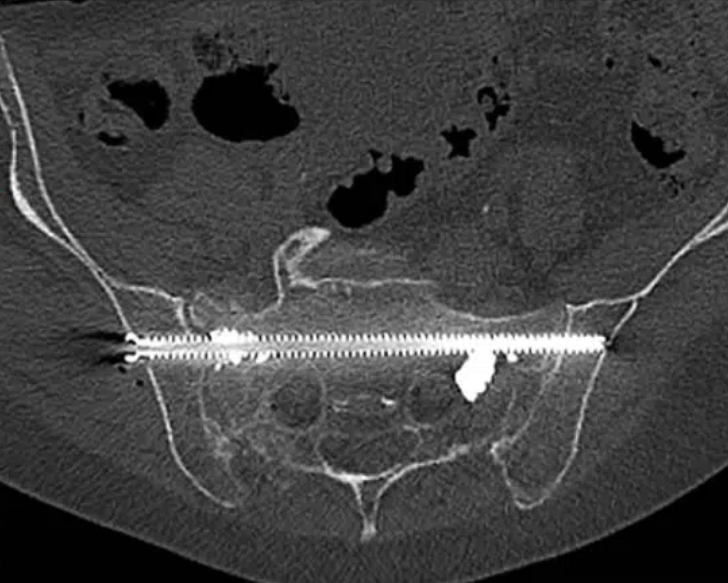

Ostéosynthèse du sacrum sur fracture en H d’origine ostéoporotique

Lors de l’ostéosynthèse percutanée, la ou les vis sont positionnées sur une canule montée sur le trocart préalablement positionnée sous controle 2D/3D. Dans la majorité des cas une injection de ciment est réalisée afin de consolider l’ ‘ensemble du montage.